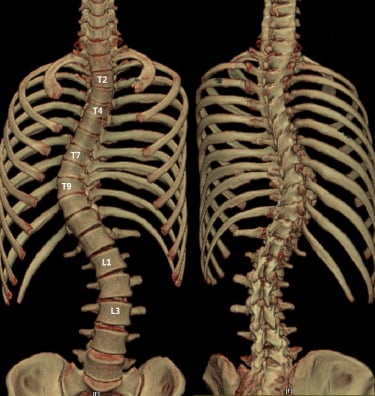

غالبًا ما يتطوّر الجنف بشكل تدريجي وقد لا يسبب ألمًا واضحًا في مراحله المبكرة. كثير من الأفراد — سواء الأطفال أو البالغين — قد لا يدركون إصابتهم بالجنف إلا بعد ملاحظة تغيّرات في وضعية الجسم أو وجود عدم تماثل واضح. ويساعد فهم العلامات الشائعة للجنف في تحديد ما إذا كان من المناسب إجراء تقييم مهني.

عند الانحناء إلى الأمام (مثل ربط الحذاء)، قد يبدو أحد جانبي القفص الصدري أو أسفل الظهر أعلى أو أكثر بروزًا من الآخر — وهي علامة شائعة على دوران العمود الفقري المرتبط بالجنف.

تساعد هذه النتائج الموضوعية على تحديد ما إذا كان الجنف موجودًا، وطبيعة انحناء العمود الفقري، وما إذا كانت هناك حاجة إلى رعاية إضافية — مثل المتابعة الدورية، أو إعادة التأهيل، أو استخدام الدعّامات — وفقًا للحالة.